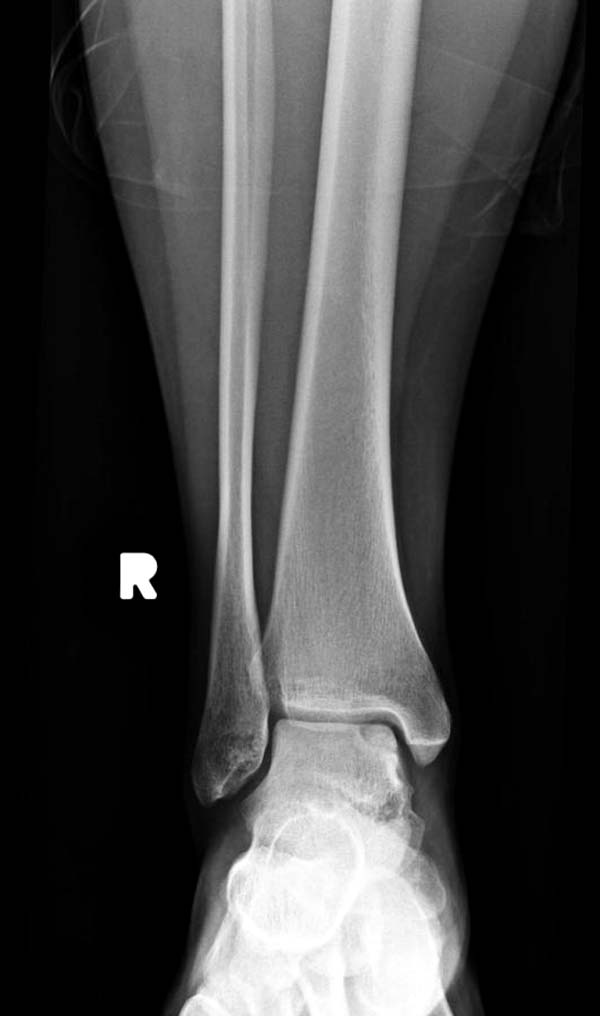

Доброго времени суток, уважаемые коллеги. Прошу помочь определиться с тактикой лечения. Пациентка 40 лет, в течение последних 8-9 мес. беспокоила боль в левом голеностопном суставе после значительной физической нагрузки (по роду деятельности вынуждена проходить в день не менее 15 км). Факт травмы отрицает. Лечилась самостоятельно, мазями и приемом НПВП. В последнее время боль стала возникать после умеренной нагрузки, присоединились отек и хромота. Прием НПВП и ограничение нагрузки до уровня бытовой болевой и отечный синдром купируют. Обратилась к нам, выявлены изменения таранной и пяточной кости, представленные на КТ. Вопрос: единственным ли выходом является артродез или можно обойтись менее радикальным вмешательством? Смущает невыраженная клиника и молодой возраст пациентки... Будем рады любой помощи со стороны уважаемого сообщества. А. Баженов, г. Екатеринбург

на рентгенограммах не всегда заметны склерозные участки, и поэтому в большинстве диагноз устанавливается поздно. Приход КТ и МРТ улучшил диагностику, и в срезах внутри кисты можно увидеть жидкость, но это не означает проявление симптоматологии. Симптомы проявляются с момента образования внутрисуставных краевых фрагментаций!